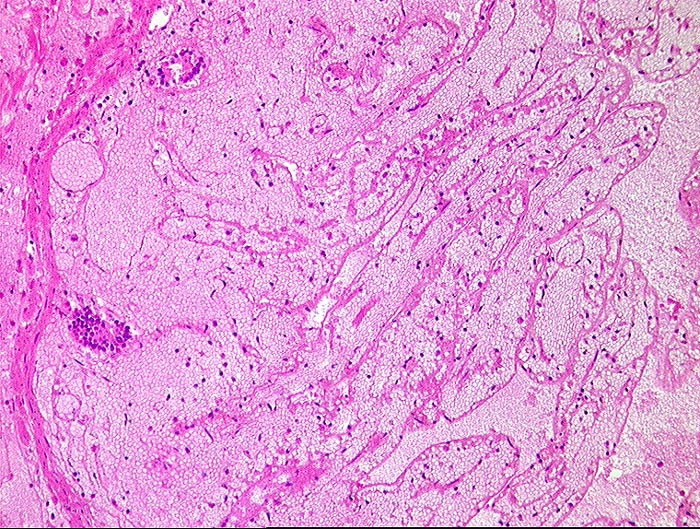

embolischer Mesenterialinfarkt

vaskulär / Durchblutungsstörung

Dünndarm

Kardiovaskuläres System

Hämorrhagische Nekrose der Mukosa.

Alter Myokardinfarkt Parietalthrombus. Frische Emboli in eröffneten Ästen der Arteria mesenterica superior.

Histologie